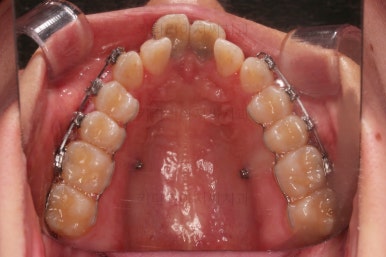

1. 초진

부산개방교합 키다리아저씨치과에 처음 내원 시 입안의 모습입니다.

전반적으로 치열이 삐뚤고요.

앞니쪽이 다물어지지 않는 개방교합(오픈바이트, open bite) 을 보였습니다.

어금니 맞물림을 보면 앵글씨 2급 부정교합 양상이어서 위아랫니가 모두 1대1로 부딪히고 있는 상태였습니다.